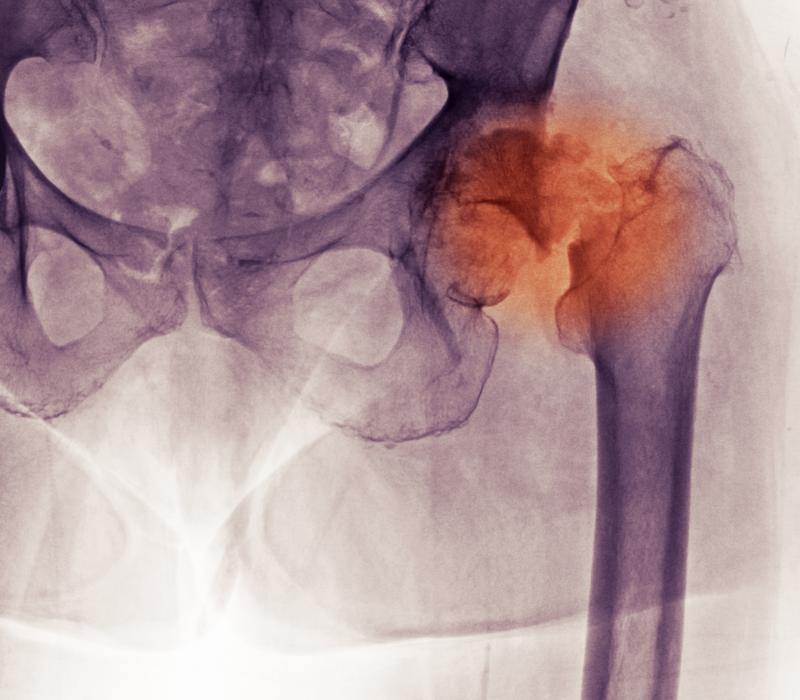

Osteoporose

Meer dan een vrouwenaandoening of een calciumprobleem

Bisfosfonaten

Osteoporose medicijnen verhogen de kans op... botbreuken